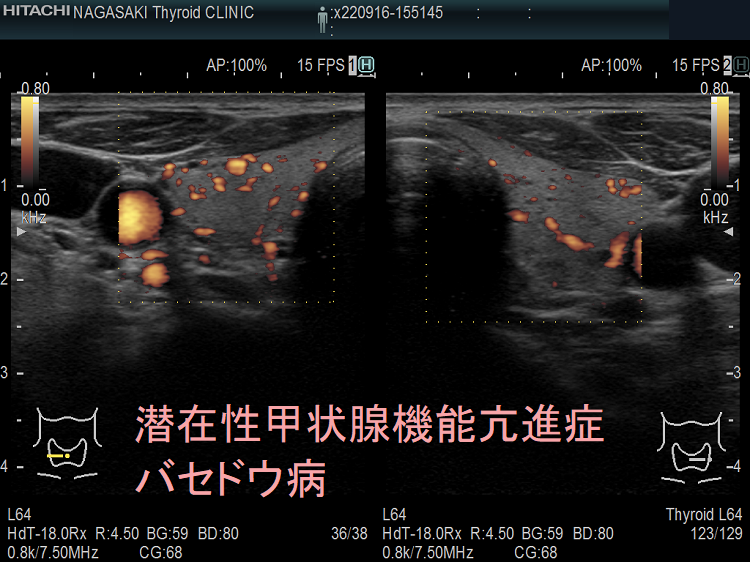

血液検査に加えて、医師は身体検査を行って、甲状腺の肥大や手の震えなど、甲状腺機能不全の兆候がないかどうかを確認します。また、甲状腺の構造を評価するために、甲状腺超音波検査などの画像検査を依頼することもあります。

原因がバセドウ病または中毒性多結節性甲状腺腫である場合、治療の成功率は高く、良好な結果が得られます。ただし、他の病気と同様、見通しは個人と治療に対する反応によって異なります。